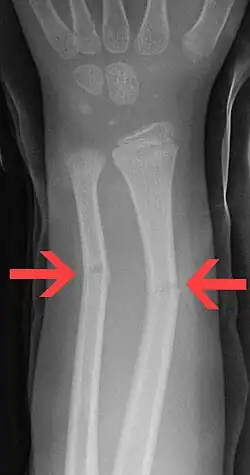

| Greenstick fractures on X-ray. | |

A greenstick fracture is a partial bone break that typically occurs in children due to their more flexible and resilient bone composition. This fracture pattern is characterized by a break on one side of the bone while the other side remains intact and bends, similar to breaking a young, green tree branch. Greenstick fractures most commonly affect the long bones of the forearm (radius and ulna) but can also occur in other long bones throughout the body. Treatment generally involves immobilization with a cast to allow proper bone healing, though in some cases, it may be necessary to realign the bone before casting.

On the side of the fracture that underwent tension, imaging may show bone cortex disruption. On the side that underwent compression, cortex may bulge outward, similar to a torus fracture.[1]

Greenstick fractures are usually identified with ease on X-ray of the affected limb, showing a long bone fracture that does not cut all the way through.[2]